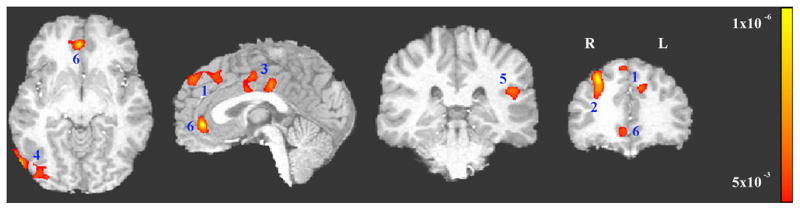

Six clusters showed a significant (p<0.005 (F value>8.76) combined with a minimum cluster size of 1226 mm3 yields an FWE corrected p<0.05) interaction between group (smoker vs. control) and cue (smoking vs. neutral) from the whole brain ANOVA analysis. These clusters include bilateral dorsal medial prefrontal cortex (dmPFC), right dorsal lateral prefrontal cortex (dlPFC), bilateral dorsal anterior cingulate cortex/cingulate cortex (dACC/CC), right middle occipital gyrus (MOG), left insula/operculum (including operculum temporale into superior temporal gyrus and operculum frontoparietale into postcentral gyrus and inferior parietal)) (I/O) and bilateral rostral anterior cingulate cortex (rACC) (see Figure 2, Table 1). Data from each of these ROIs were used in subsequent secondary analyses.

Figure 2.

Significant interactions (FWE corrected p<0.05, i.e., uncorrected p<0.005 and minimal volume=1226mm3) between group (smokers vs. controls) and stimulus cue type (smoking vs. neutral). 1: bilateral dorsal medial prefrontal cortex (dmPFC), 2: right dorsal lateral prefrontal cortex (dlPFC); 3: bilateral dorsal anterior cingulate cortex/cingulate cortex (dACC/CC)), 4: right middle occipital gyrus (MOG), 5: left Insula/operculum, and 6: bilateral rostral anterior cingulate cortex (rACC).